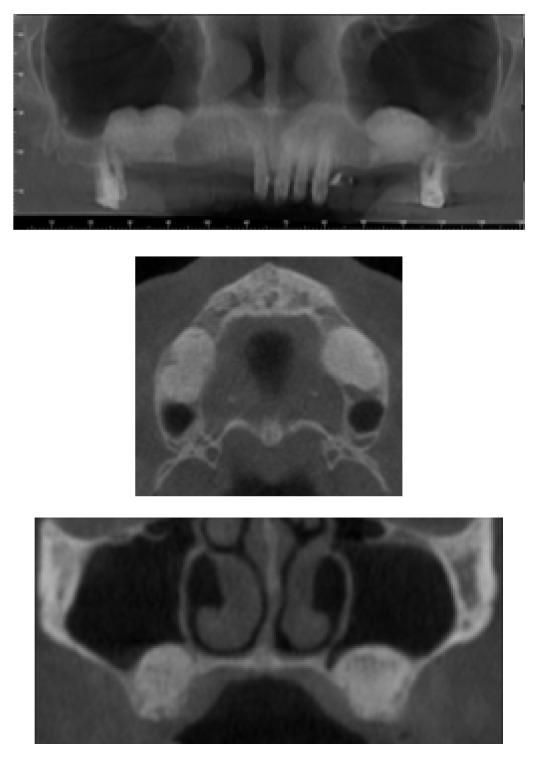

Aim. The aim of this study was to assess the success and the survival rate of dental implants placed in augmented bone after sinus lifting procedures. Material and Methods. 31 patients were mainly enrolled for a residual upper jaw crest thickness of 3 mm. CBCT scans were performed before and after the augmentation technique and at the follow-up appointments, at 3, 6, 12, 24, and up to 60 months. The follow-up examination included cumulative survival rate of implants, peri-implant marginal bone loss, and the height of sinus floor augmentation. Results. This retrospective study on 31 patients and 45 implants later inserted in a less than 3 mm crest showed excellent survival rates (99.5%), one implant was lost before loading due to an acute infection after 24 days, and two implants did not osteointegrate and were removed after 3 months. The radiological evaluation showed an average bone loss of 0.25 mm (±0.78 mm) at the first follow-up appointment (3 months) up to 0.30 mm (±1.28 mm) after 60-month follow-up. Conclusion. In this study it was reported how even in less than 3 mm thick crest a transcrestal technique can predictably be used with a long-term clinical and radiological outcome, giving patients excellent stability of the grafted material and healthy clinical results.

目的。本研究的目的是评估在鼻窦提升术后植入增骨部位的牙种植体的成功率和存活率。材料与方法。主要纳入了31例上颌嵴剩余厚度为3毫米的患者。在增骨技术前后以及随访时进行CBCT扫描,随访时间为3、6、12、24个月直至60个月。随访检查包括种植体的累积存活率、种植体周围边缘骨丢失以及鼻窦底提升的高度。结果。这项对31例患者和后来植入不足3毫米嵴中的45颗种植体的回顾性研究显示出优异的存活率(99.5%),一颗种植体在加载前因24天后的急性感染而丢失,两颗种植体未骨整合并在3个月后被取出。放射学评估显示,在首次随访(3个月)时平均骨丢失为0.25毫米(±0.78毫米),至60个月随访后为0.30毫米(±1.28毫米)。结论。在本研究中报告了,即使在上颌嵴厚度不足3毫米的情况下,穿嵴技术仍可预测地用于获得长期临床和放射学结果,为患者提供移植材料的优异稳定性和健康的临床结果。